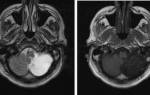

Онкологи считают, что при нарастающих головных болях с прочими необъяснимыми симптомами (обмороками, ухудшением памяти, выпадением полей зрения, давлением на глазные яблоки и др.) в первую очередь следует исключить опухолевую патологию

Что покажет МРТ головы с контрастом

После контрастирования при МРТ детализация мелких структур значительно выше. Магнитно-резонансную томографию с усилением предпочитают онкологи, так как можно увидеть контуры опухоли, определить степень ее инвазии (прорастание в близлежащие ткани), диагностировать метастазы. МРТ с введением контраста лучше показывает изменения после операции, патологические очаги в головном мозге на фоне рассеянного склероза, при болезни Альцгеймера. Чаще используют препараты на основе хелатов гадолиния. Мировая практика подтверждает высокий профиль безопасности: при грамотном применении осложнения встречаются крайне редко.